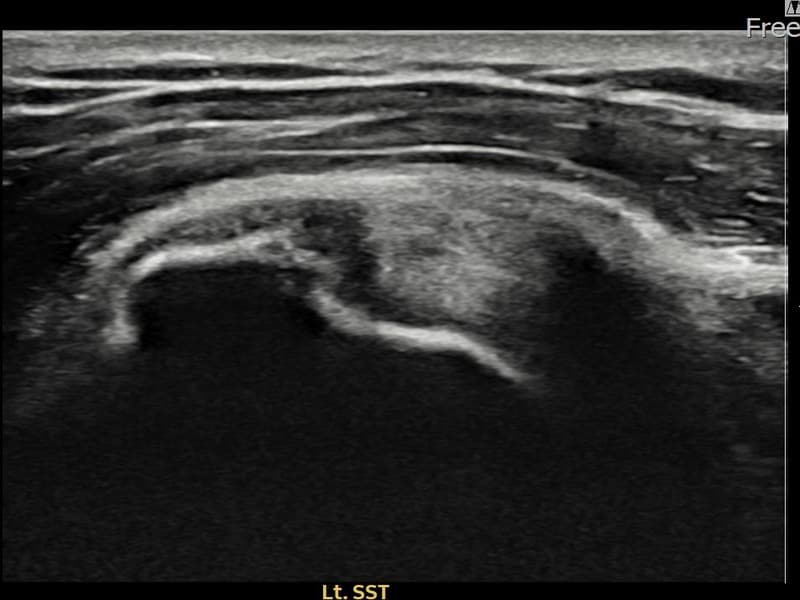

术前

术前超声确认左侧 冈上肌腱 部分撕裂,左侧冈上肌腱回声不连续伴肌腱缺损(7mm × 3mm (肌腱厚度约30%缺损))。术后超声显示撕裂部位充满再生组织,肌腱连续性恢复,回声模式正常化。

该患者持续肩痛。详细超声检查确认左侧 冈上肌腱 部分撕裂(缺损:7mm × 3mm (肌腱厚度约30%缺损))。在超声引导下实施非手术缩小缝合术。术后佩戴支具约4-6周,随后进行分阶段康复锻炼。随访超声确认肌腱连续性恢复、结构稳定,患者顺利回归日常生活。